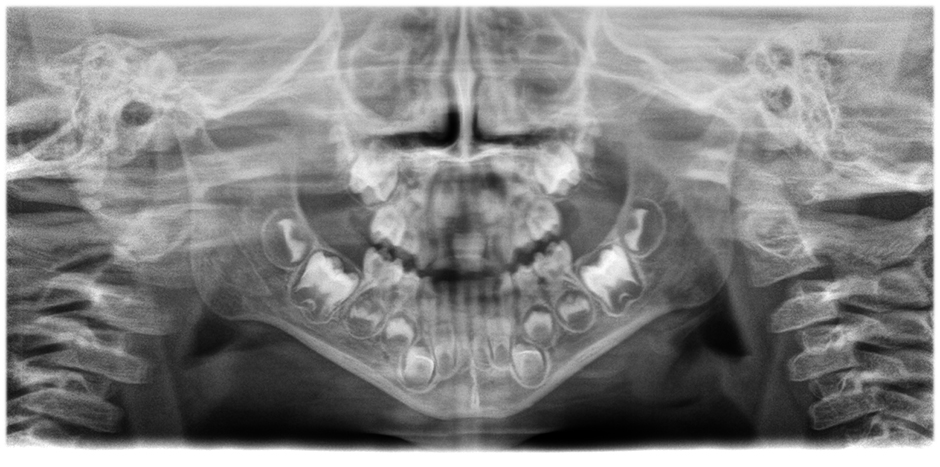

• Panoramabilder von herausragender Klarheit und Schärfe

mit dem innovativen 21-Layer-Autofokussystem, das nahtlos in eine Patientenpositionskorrektur integriert ist.

Bewegen Sie den Slider, um den Unterschied zu sehen (linkes Bild ohne, rechtes Bild mit Autofokus und korrigierter Patientenposition).